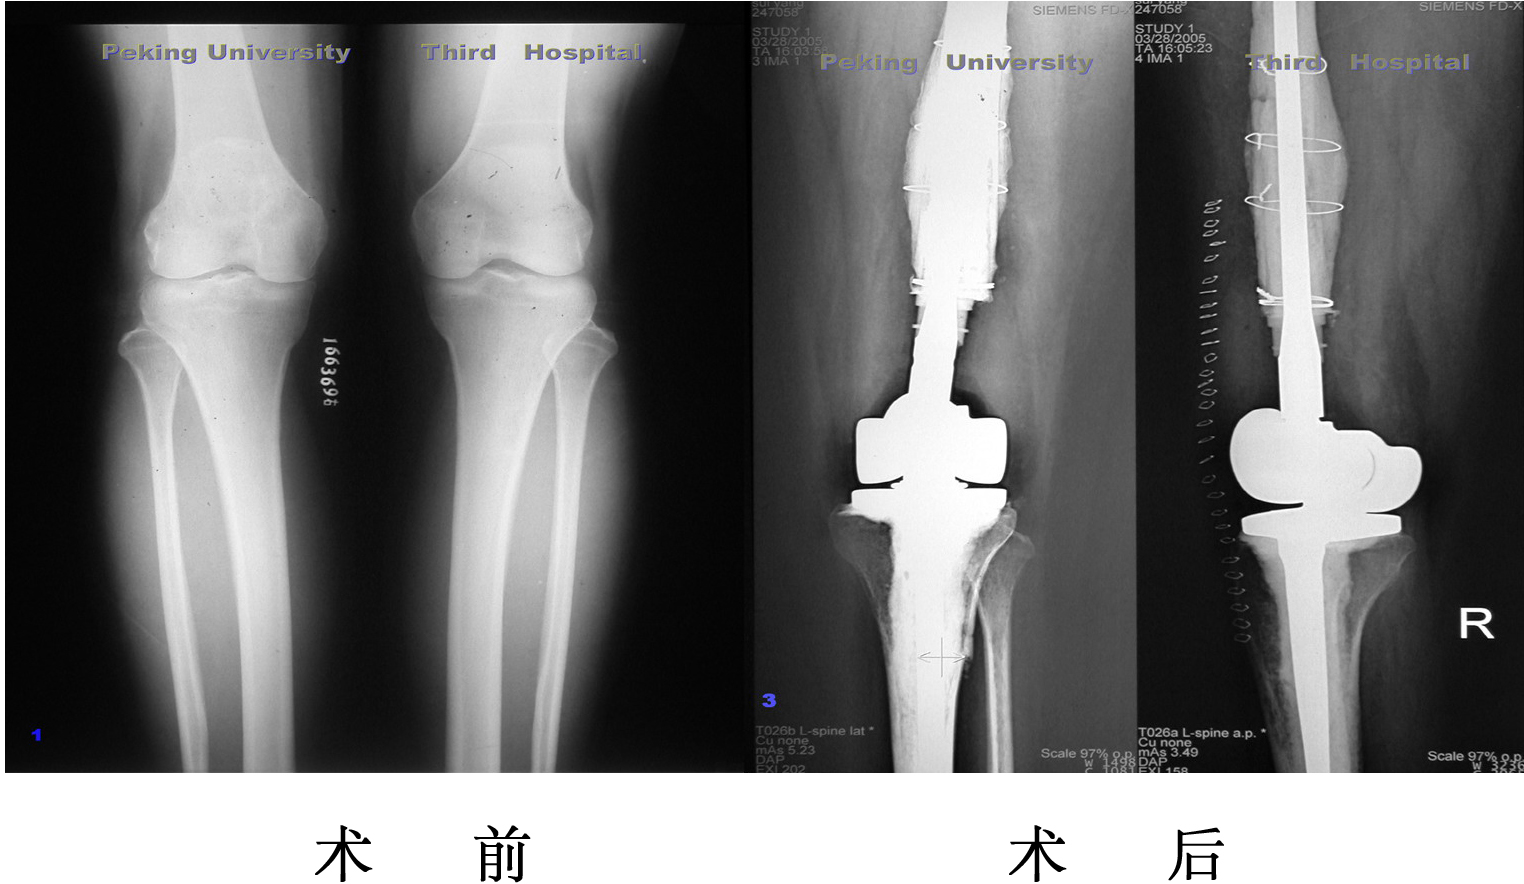

单髁膝关节置换术后8年,塌陷,接受全膝关节表面置换术

单髁置换

膝关节内侧间隙狭窄,适合单髁置换,手术后恢复快,

关节活动最大限度保留